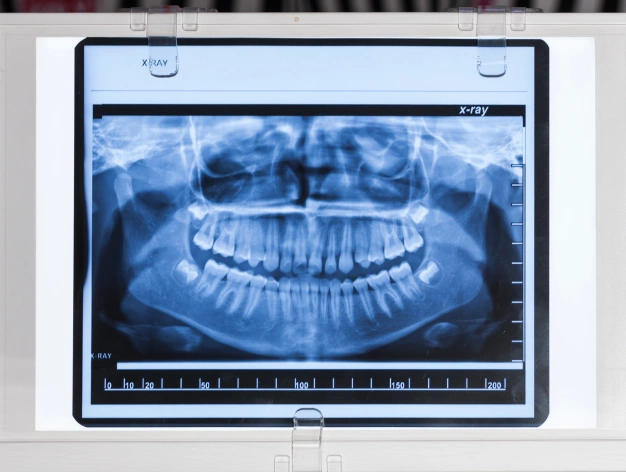

In order to provide you with the best possible care, it is essential for our dentists to accurately evaluate and diagnose your oral health. One of the state-of-the-art tools we use to do that is panoramic X-rays. While standard X-rays, called bitewing X-rays, provide us with a view of a few teeth and the supporting bone structure, panoramic X-rays allow us to view the full upper and lower dental arches, including all of the teeth, the upper and lower jawbones, and the surrounding facial structures.

This broader perspective gives our team valuable insight into your overall oral health and helps us plan treatment with confidence.